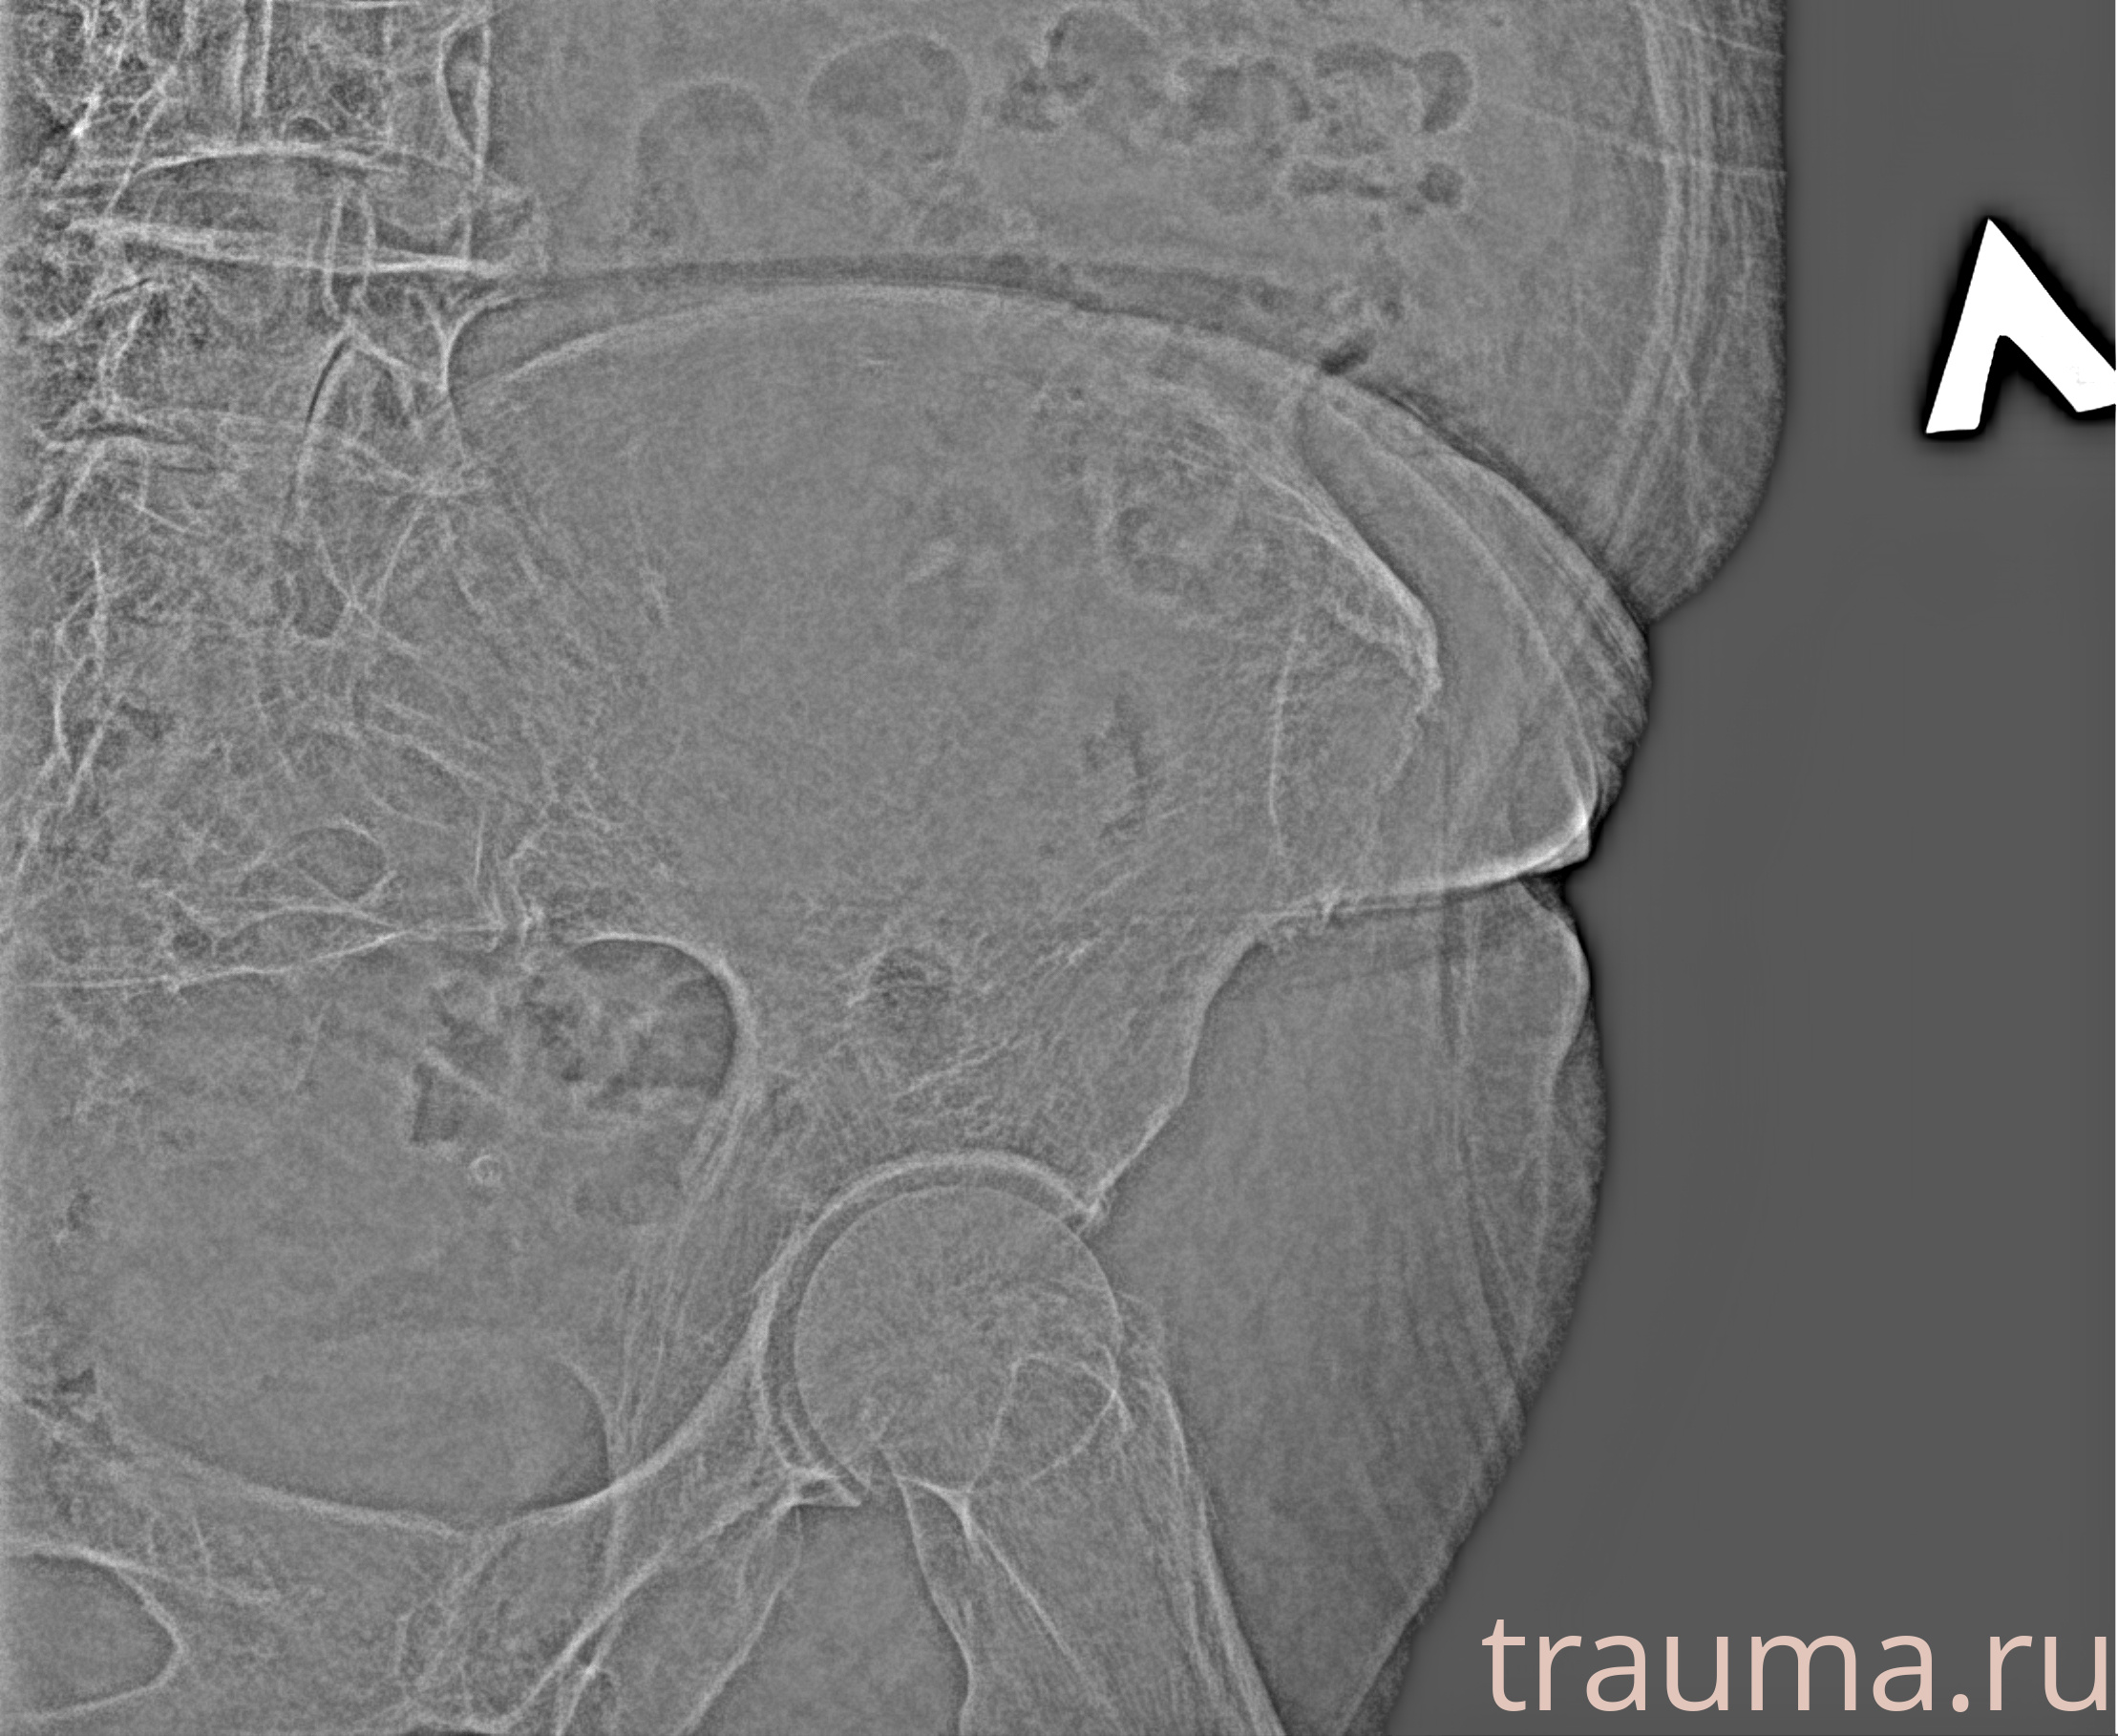

Рентгенограммы

Рентген на дому: по вашему адресу приезжает врач-рентгенолог, травматолог-ортопед с мобильным рентгеновским аппаратом, проводит диагностику травмы или заболевания, делает необходимые рентгенограммы, дает рекомендации по дальнейшему лечению. Получить качественные снимки в домашних условиях возможно благодаря уникальной методике, разработанной МосРентген Центром для института  Склифосовского